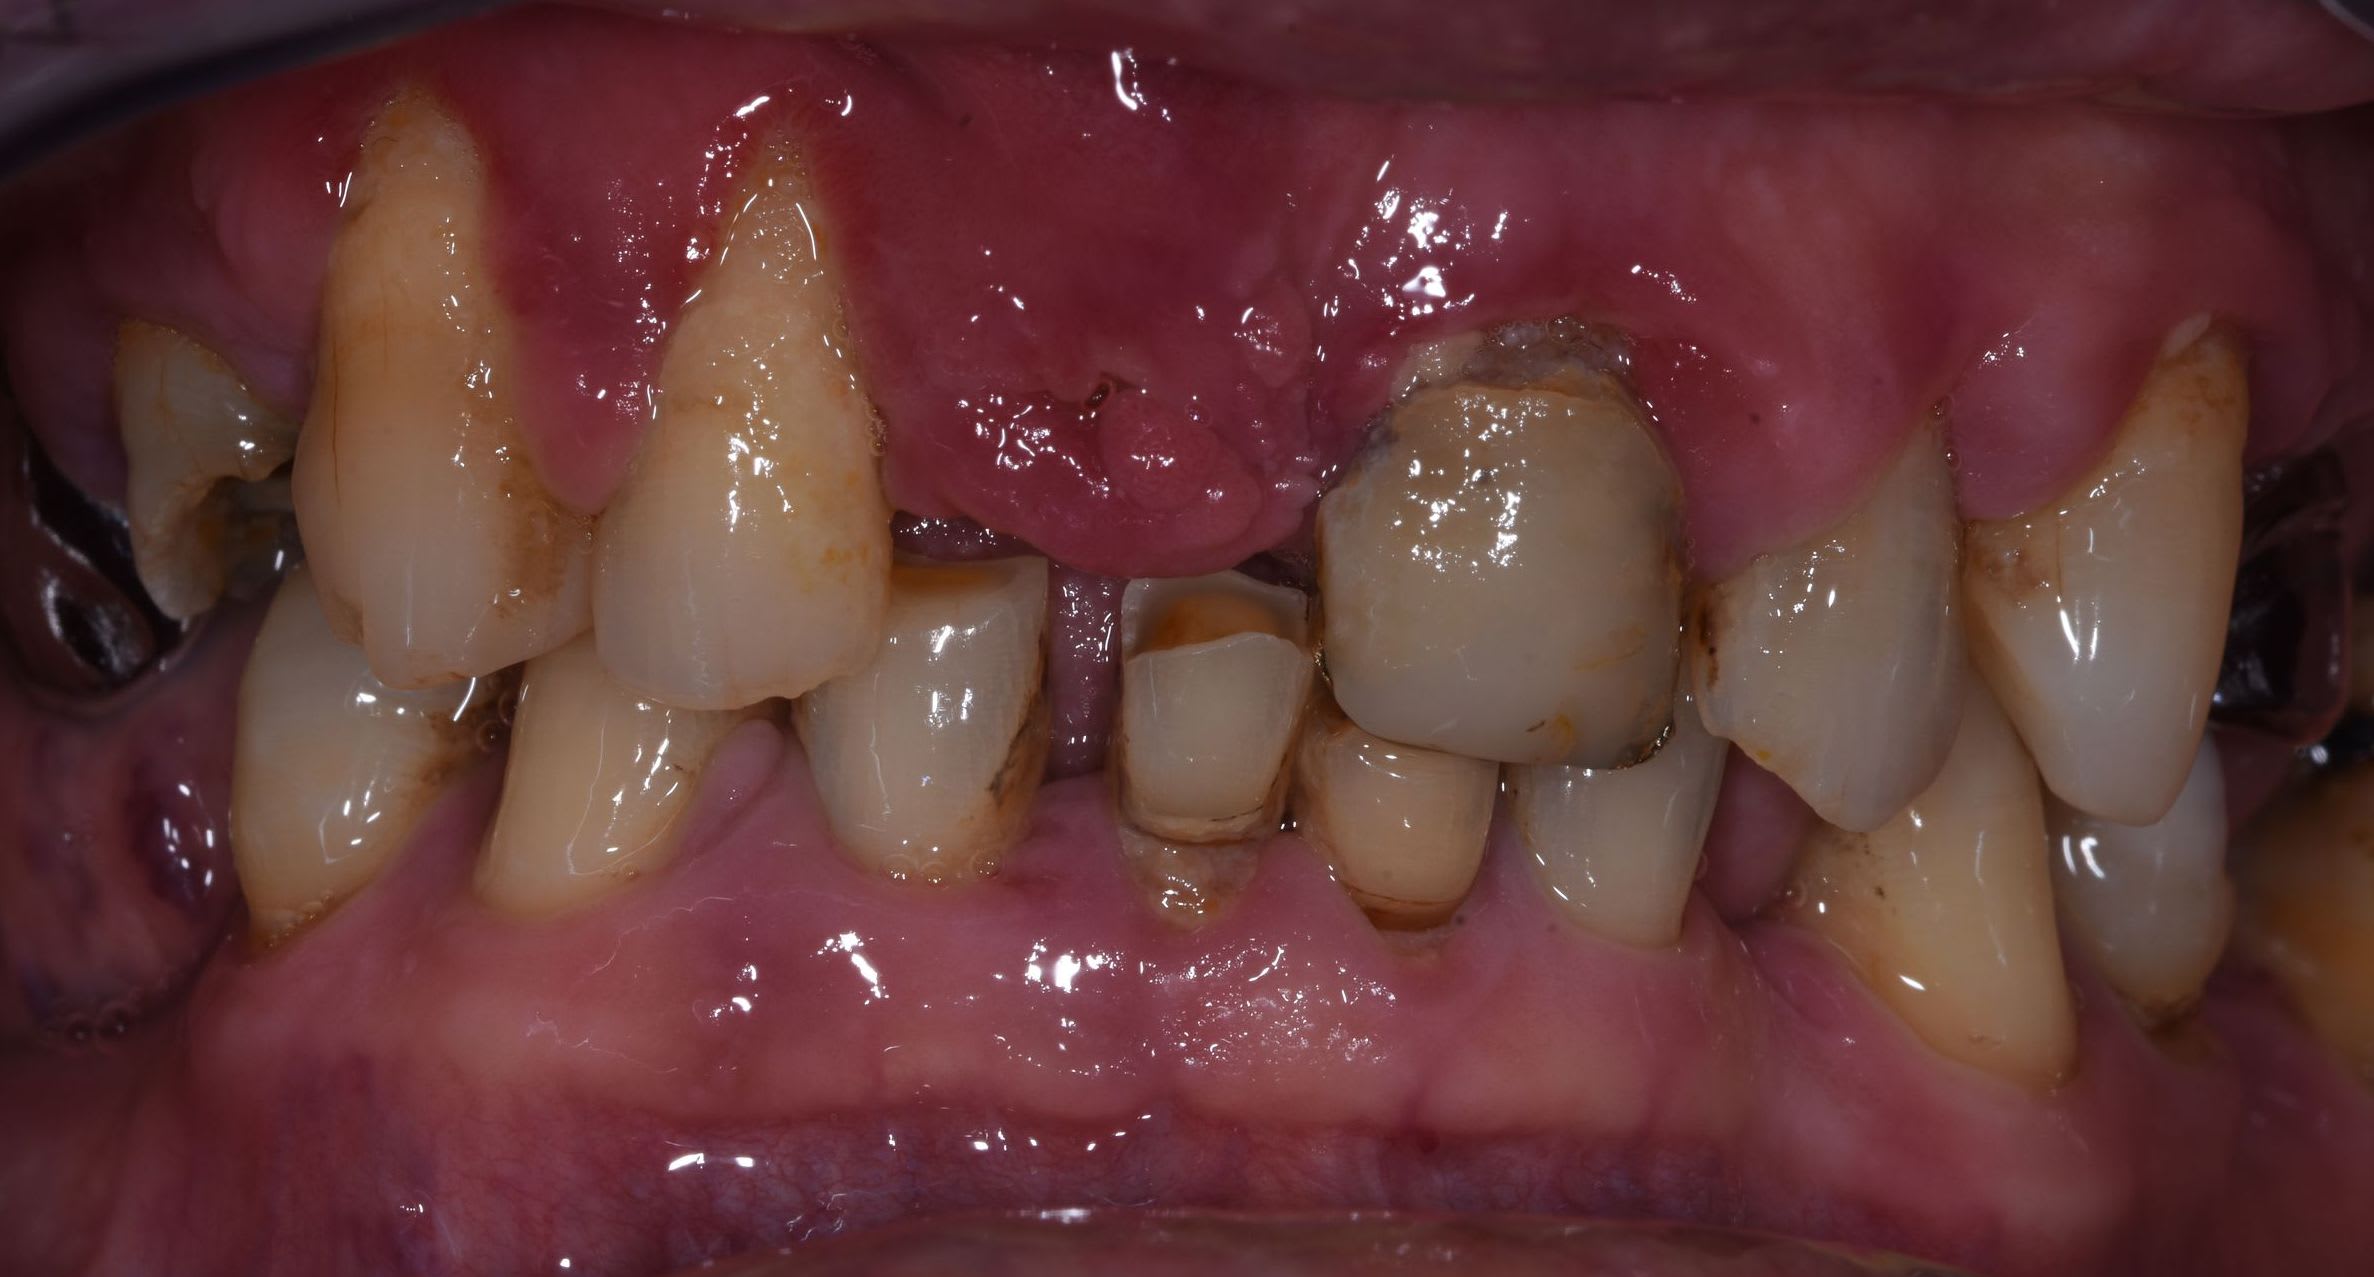

J'ai un patient de 60 ans, bonne santé générale. Rémission de maladie auto-immune lourde mais stable depuis 3 ans. Non fumeur.

La première consultation, il y avait de la plaque partout.

Sa demande : garder tout ce qui est possible.

Une motivation au brossage, un det et un surfaçage + tard, histoire de remettre les choses en état, je me retrouve avec ce type de gencive : voir les photos.

La situation est-elle sauvable pour les incisives (Gépé va répondre titane je suppose) ?

tu as remarqué comme le bas est moins altéré que le haut ? pb occlusal majeur .

Des papilles hyperplasiques au delà de leur position physiologique et un rapport dentaire-os 1/2. Tu dois taper dedans à la turbine pour ramener l’ensemble à plat. Raccourcir tes chicots. Mais avant calage postérieur ++++, sans ça, ne rien toucher. Là, c’est de la dentisterie de guerre.

Tu as des migrations secondaires et une dv effondrée, tu ne peux que coiffer au moins toutes les maxillaires entre autre pour rétablir un angle I/i correct, et des courbes compatibles.